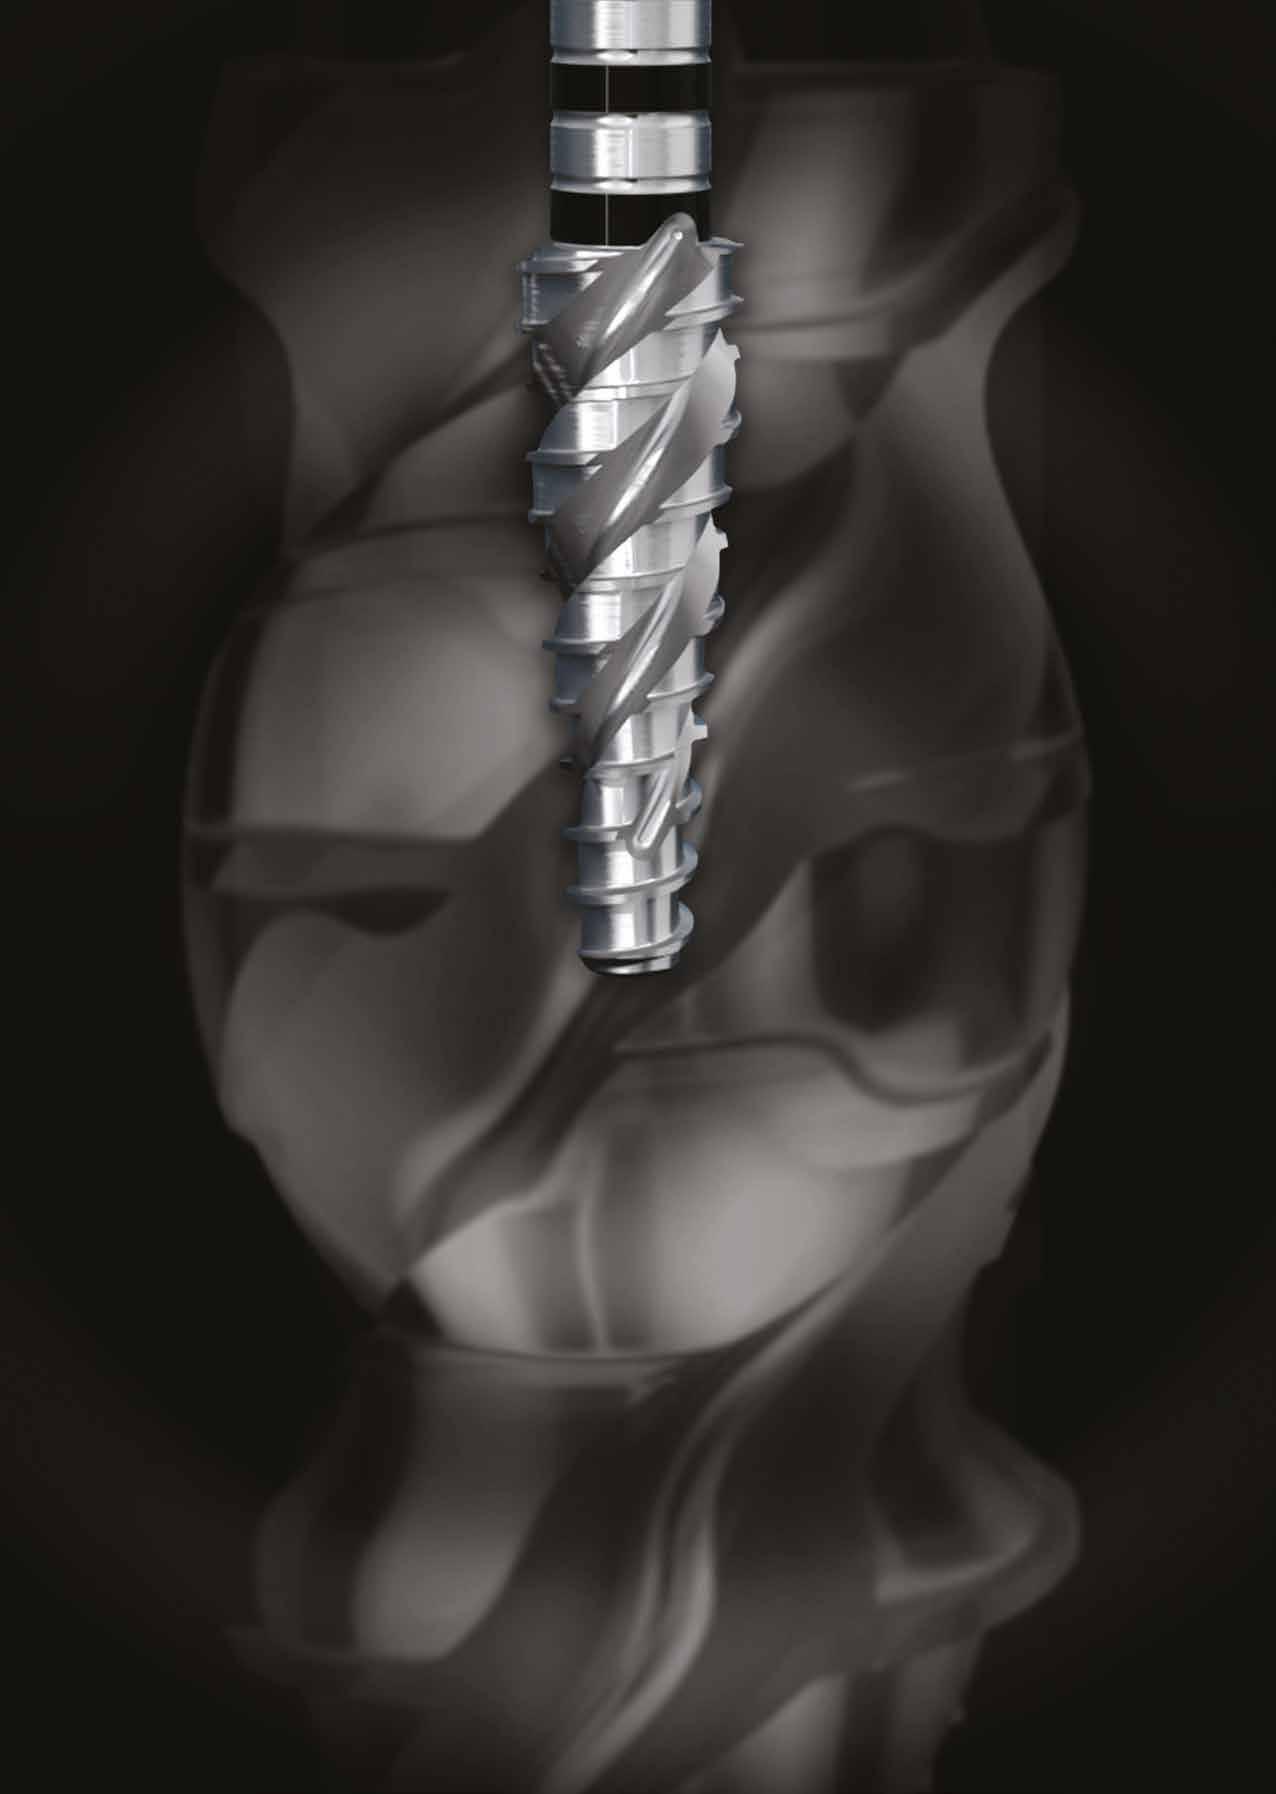

A részleges extrakció befejezése után következhet az implantátumágy preparálása a gyártó utasításai szerint (6.

kép). A bemutatott esetben Nobel Replace CC 4,3x13mm implantátumot helyeztünk be, amely a bukkális oldalon direkt kontaktusba került a megmaradt foggyökérdarabbal (7. kép). Az alveolus oldalfalai és a körszimmetrikius implantátum közötti hézag kitöltésére bovin eredetű xenograftot (Creos S xenogain) használtunk (8. kép). A hasonló